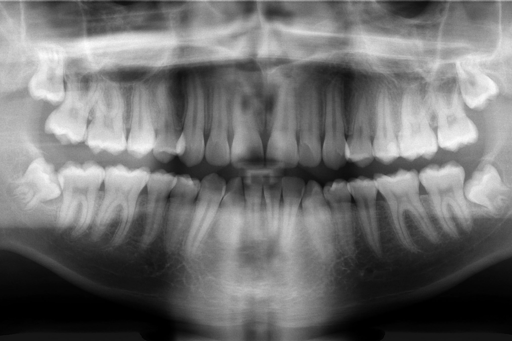

Using an antibody treatment to suppress USAG-1 in ferrets led to the development of supernumerary teeth. In regular speak, that means “more teeth than you would typically expect a ferret to have.” Credit: Research paper

It’s believed humans may have buds for a third set of teeth already lurking, just waiting to be activated. Credit: research paper